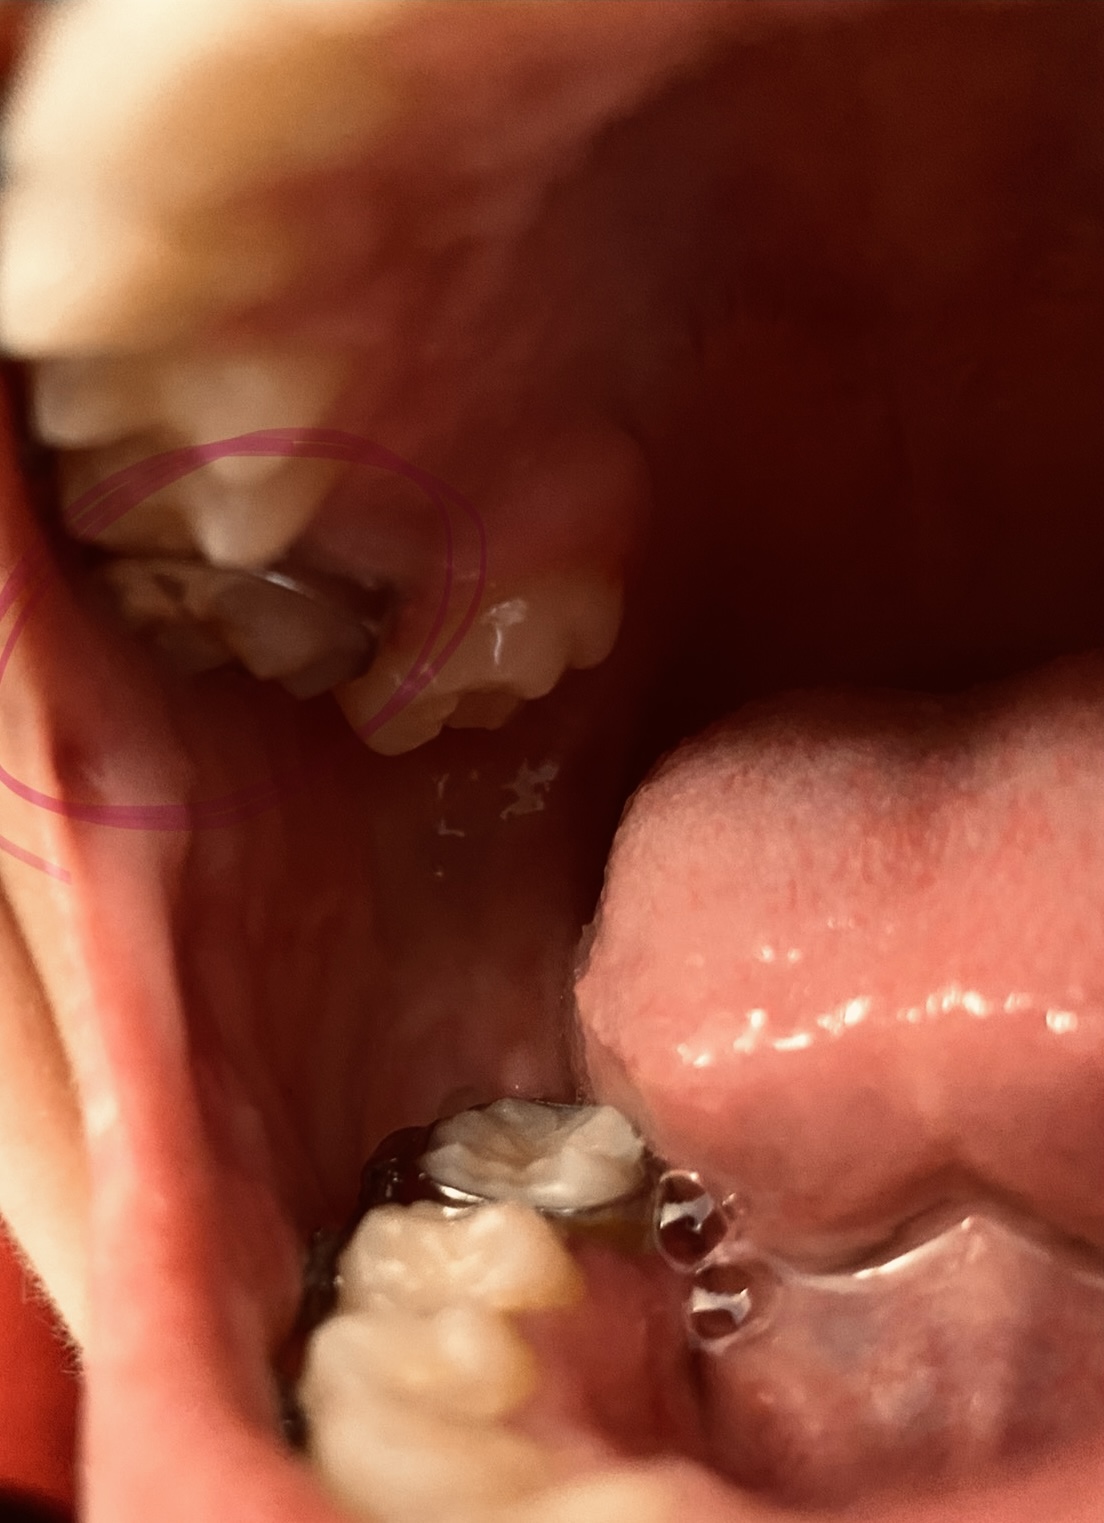

Hello, I had a root canal done on tooth #13 a few years ago, but there was so much decay on the tooth that my dentist had to drill most of the tooth. Because of how little of the tooth is left the crown does not fit correctly, leaving a bit of a gap. The dentist that did the root canal suggested that in the future I get it extracted and get an implant, but also suggested that I get it extracted and instead of getting an implant that I get braces to correct the crowding on my upper and lower teeth and could reduce the need for an implant. I was wondering if this is something that is possible?